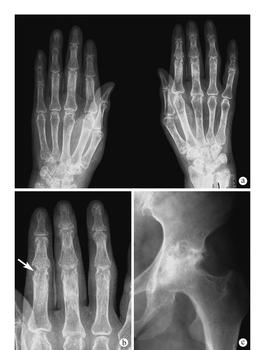

类风湿关节炎我们人人都晓得但不是人人都了解的,如果在病人在不晓得状况下发病的话,而且身体外在的表现很显着,那就是我们会常常称为急性类风湿关节炎。假设患上急性的风湿疾病而且不能够及时治疗的话,会给病人们带来无法估计的身体影响。为了我们能够非常好的晓得急性类风湿关节炎的表现,活跃协作治疗。下面请骨科专家为我们盘点急性类风湿关节炎的表现,希望对病人们有一定的帮忙。

2.多处关节呈现并发症,首要是以大关节为首要表现,有些有些会呈现红热、肿胀、痛苦的显着的特征。炎症消退后关节正。还可能会有心脏炎等风湿热的其他表现。